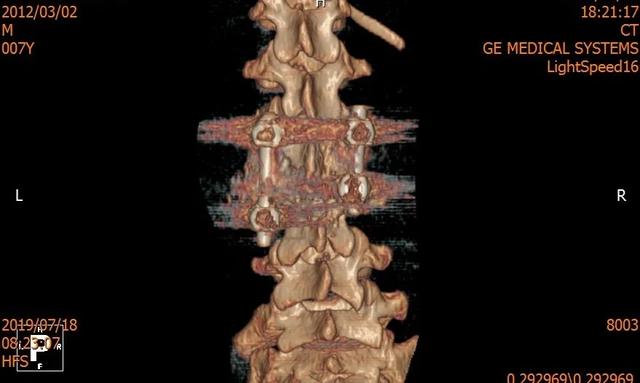

医疗团队本着对少年儿童的关爱,把担子压在自己肩上,准备得仔细又仔细。术前还以患者畸形脊柱的超薄 CT 为基础,运用最先进的 3D 打印技术构建了患者脊柱模型,并利用数字模拟技术模拟了患者内固定的最佳植入路径,反复模拟手术,做好了充分的术前准备。

术前 CT & 3D 打印

术后 CT